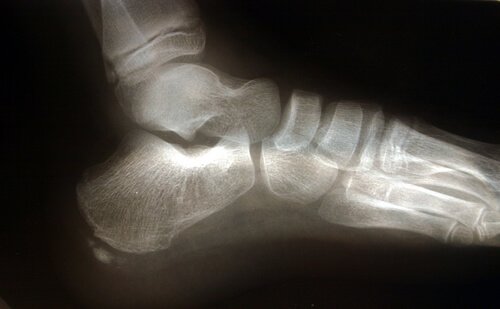

足底筋膜炎常與骨刺的存在有關,儘管這不是一個決定因素。

足部解剖學

有幾種解剖學結構在足底筋膜的過度負荷中扮演重要角色。

阿基里斯腱是一條腓腸肌連接跟骨的肌腱。阿基里斯腱的回縮會觸發跟骨的壓力增加,進而導致足底筋膜的壓力增加。

另一個解剖學結構的重要因素是腳掌著地的方式,也就是說,脚是如何接觸地面的。扁平足或者足部有過度內旋的傾向,會伸展足底筋膜,進而增加組織額外壓力而造成撕裂的風險。